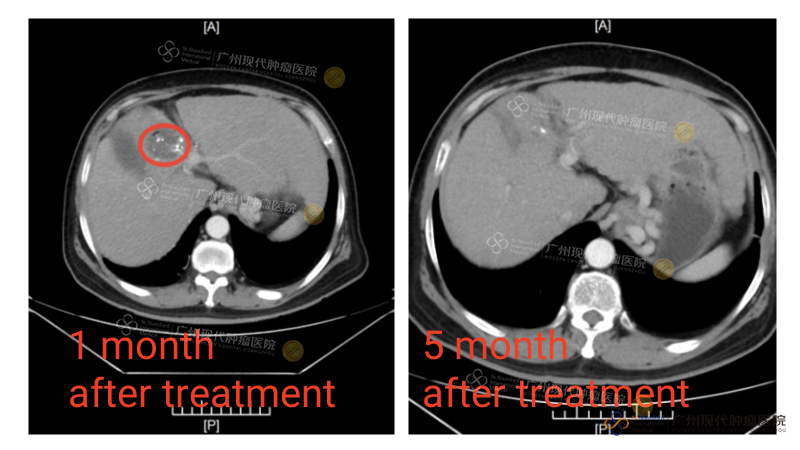

CT tumor Vo Van Hoa sebelum dan sesudah pengobatan

Vo Van Hoa, seorang pasien kanker hati, mengalami gejala seperti demam ringan akibat kelelahan berulang, nyeri dan rasa penuh di perut kanan atas, sakit kepala, serta gangguan pada saraf wajah yang menyebabkan mati rasa dan nyeri di rahang serta bibir. Pada tahun 2019, ia didiagnosis menderita kanker hati tipe masif. Karena tidak ingin menjalani operasi konvensional di rumah sakit lokal, ia memilih datang ke Modern Cancer Hospital Guangzhou. Di RS ini, ia menjalani pengobatan minimal invasif berupa Intervensi dikombinasikan dengan NanoKnife. Hasilnya, tumor berukuran 70×60mm mengalami nekrosis total tanpa ada sisa jaringan aktif. Kini, enam tahun setelah pengobatan, tumornya belum pernah kambuh, dan ia telah kembali menjalani kehidupan normal.